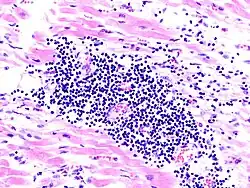

Bakterielle Myokarditis

Mikro: Zentral Bakterienkolonien in der Kapillare umsäumt von Immunozyten.

Makro: Kleine, gelbe, punktförmige Mikroabszesse.